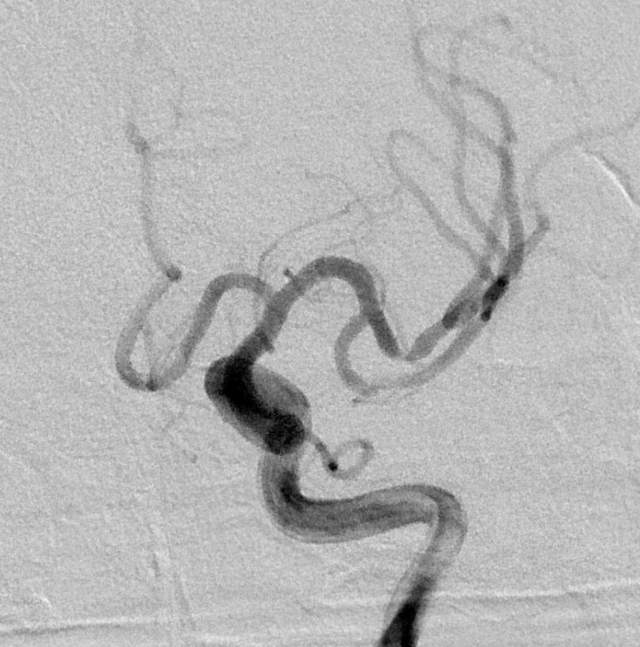

不干预吧,毕竟残存了一些功能障碍,还可能存在再次卒中的风险。通过多学科诊疗(MDT)和脑血管造影(金标准)后,进一步确认了狭窄的存在,左侧大脑中动脉上干血管存在重度狭窄,下干轻度狭窄。手术的难度在于狭窄的部位处于血管弯曲的部位,另外还要为下干预留日后可能干预的空间。

手术顺利完成,狭窄改善,血管直径基本恢复正常。